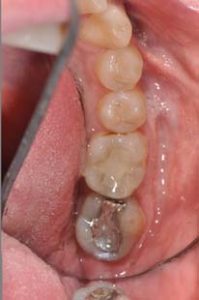

The patient was a 35-year-old male who presented with recurrent decay on a large amalgam filling on the lower left second molar. It was determined that it would not be possible to salvage the restoration and a full crown would be necessary. The patient was informed the crown could be made the same day using the True Definition Scanner, and the PlanMill system to mill the restoration chairside.

The patient was anesthetized, and the True Definition Scanner was used to scan the opposing arch and the bite while the anesthesia took effect. The defective area of the amalgam was then removed, and the rest of the tooth was prepped. A two-cord technique was used for gingival retraction and the prep was scanned, with the scanner quickly picking up the margins.

The crown was then designed in 5 to 10 minutes using the Planmeca software, after which it was milled in approximately 20 minutes. The crown was cleaned and polished, then tried in the mouth to confirm its fit. Because of the accuracy of the True Definition scanner, no adjustments were necessary. The tooth was then isolated and 3M™ ESPE™ Scotchbond™ Universal Adhesive was applied. The bonding surface of the restoration was sandblasted and cleaned, and then cemented with 3M™ ESPE™ RelyX™ Ultimate Cement.